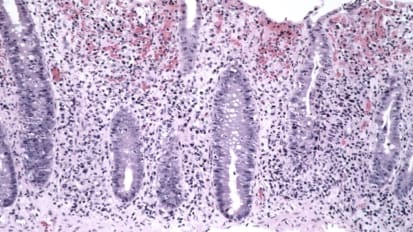

Lower GI Pathology

Review of lower GI pathology via a case-based lecture with Boards-style questions and answers.